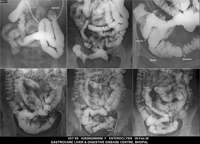

Section: ENTEROCLYSIS

Total: 205 Cases